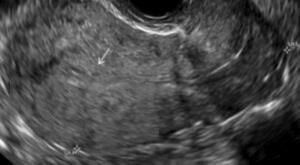

В учебном пособии на современном уровне освещены вопросы диагностики эндометриоза различной локализации. Предназначено для врачей акушеров-гинекологов с целью формирования научно-обоснованного подхода в диагностике эндометриоза и его локализаций с целью обнаружения заболевания на ранних стадиях и сохранения репродуктивного здоровья женщины.